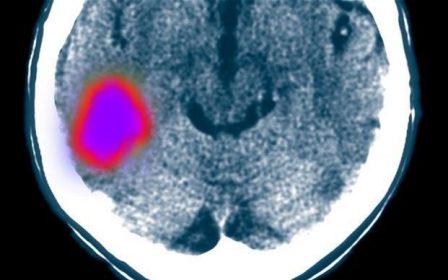

پس از سكته، مغز قابليت خودترميمي دارد

محققان مي گويند كه مغز قابليت خود ترميمي نواحي آسيب ديده را دارد و جلوگيري از طي شدن اين روند، مي تواند از بهبودي كامل مغز جلوگيري كند.

اما اكنون محققان مي گويند كه مغز قابليت خود ترميمي نواحي آسيب ديده را دارد و جلوگيري از طي شدن اين روند، مي تواند از بهبودي كامل مغز جلوگيري كند.

وقتي سكته مغزي اتفاق مي افتد، سلول هاي عصبي در ناحيه آسيب ديده مغز مي ميرند و التهابي را ايجاد مي كنند كه در نتيجه آن، سلول ها سيستم ايمني بدن از جمله مونوسيت ها جذب مي شوند.